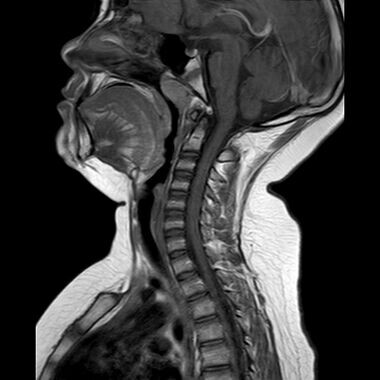

👆Посмотрим внимательнее на этот снимок, а теперь вопрос 👆

Перед вами реальный снимок пациента с изменениями в области шейно-грудного перехода.

Как думаете, какие симптомы беспокоят этого человека?